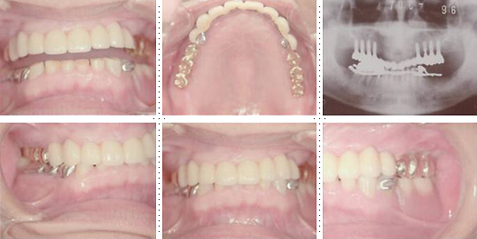

症例2

62才 女性

上顎は総義歯、下顎はブリッジと局部床義歯が装着。義歯は違和感があり、食事も不便を感じ、審美的にも人前にでるのが苦痛に感じていました。この状態を打破するためにも、「インプラント治療に自分の人生を賭けてみたい」という覚悟で来院されました。インプラント手術に対する恐怖心も強くお持ちでした。このような骨幅が狭いケースでは、X線撮影と共にCT撮影による画像診断とインプラント埋入シミュレーションが重要です。

下顎は両側犬歯を残し、他は抜歯。インプラント7本埋入。 上顎はインプラント8本埋入。 インプラント手術を受けられる患者さんは、前の晩眠れない程の不安感、恐怖心を持って来院されます。実際には麻酔注射は痛みを感じず、インプラント手術も痛みも無く、短時間(1本平均3分)で終わるという、当院独自のテクニックにより、2回目からのインプラント手術は気楽になるようです。 前歯は仮歯の段階で患者さん、歯科医、技工士の三者で、審美性・機能性の面から10回以上形態修正を繰り返し検討した後、上・下顎共に前歯・小臼歯はセラミック(MB)クラウン、大臼歯はゴールドクラウンを装着。ご本人とご家族の方にも、「アンチエイジングには、審美インプラント治療が一番効果あり」と大変喜んで頂きました。